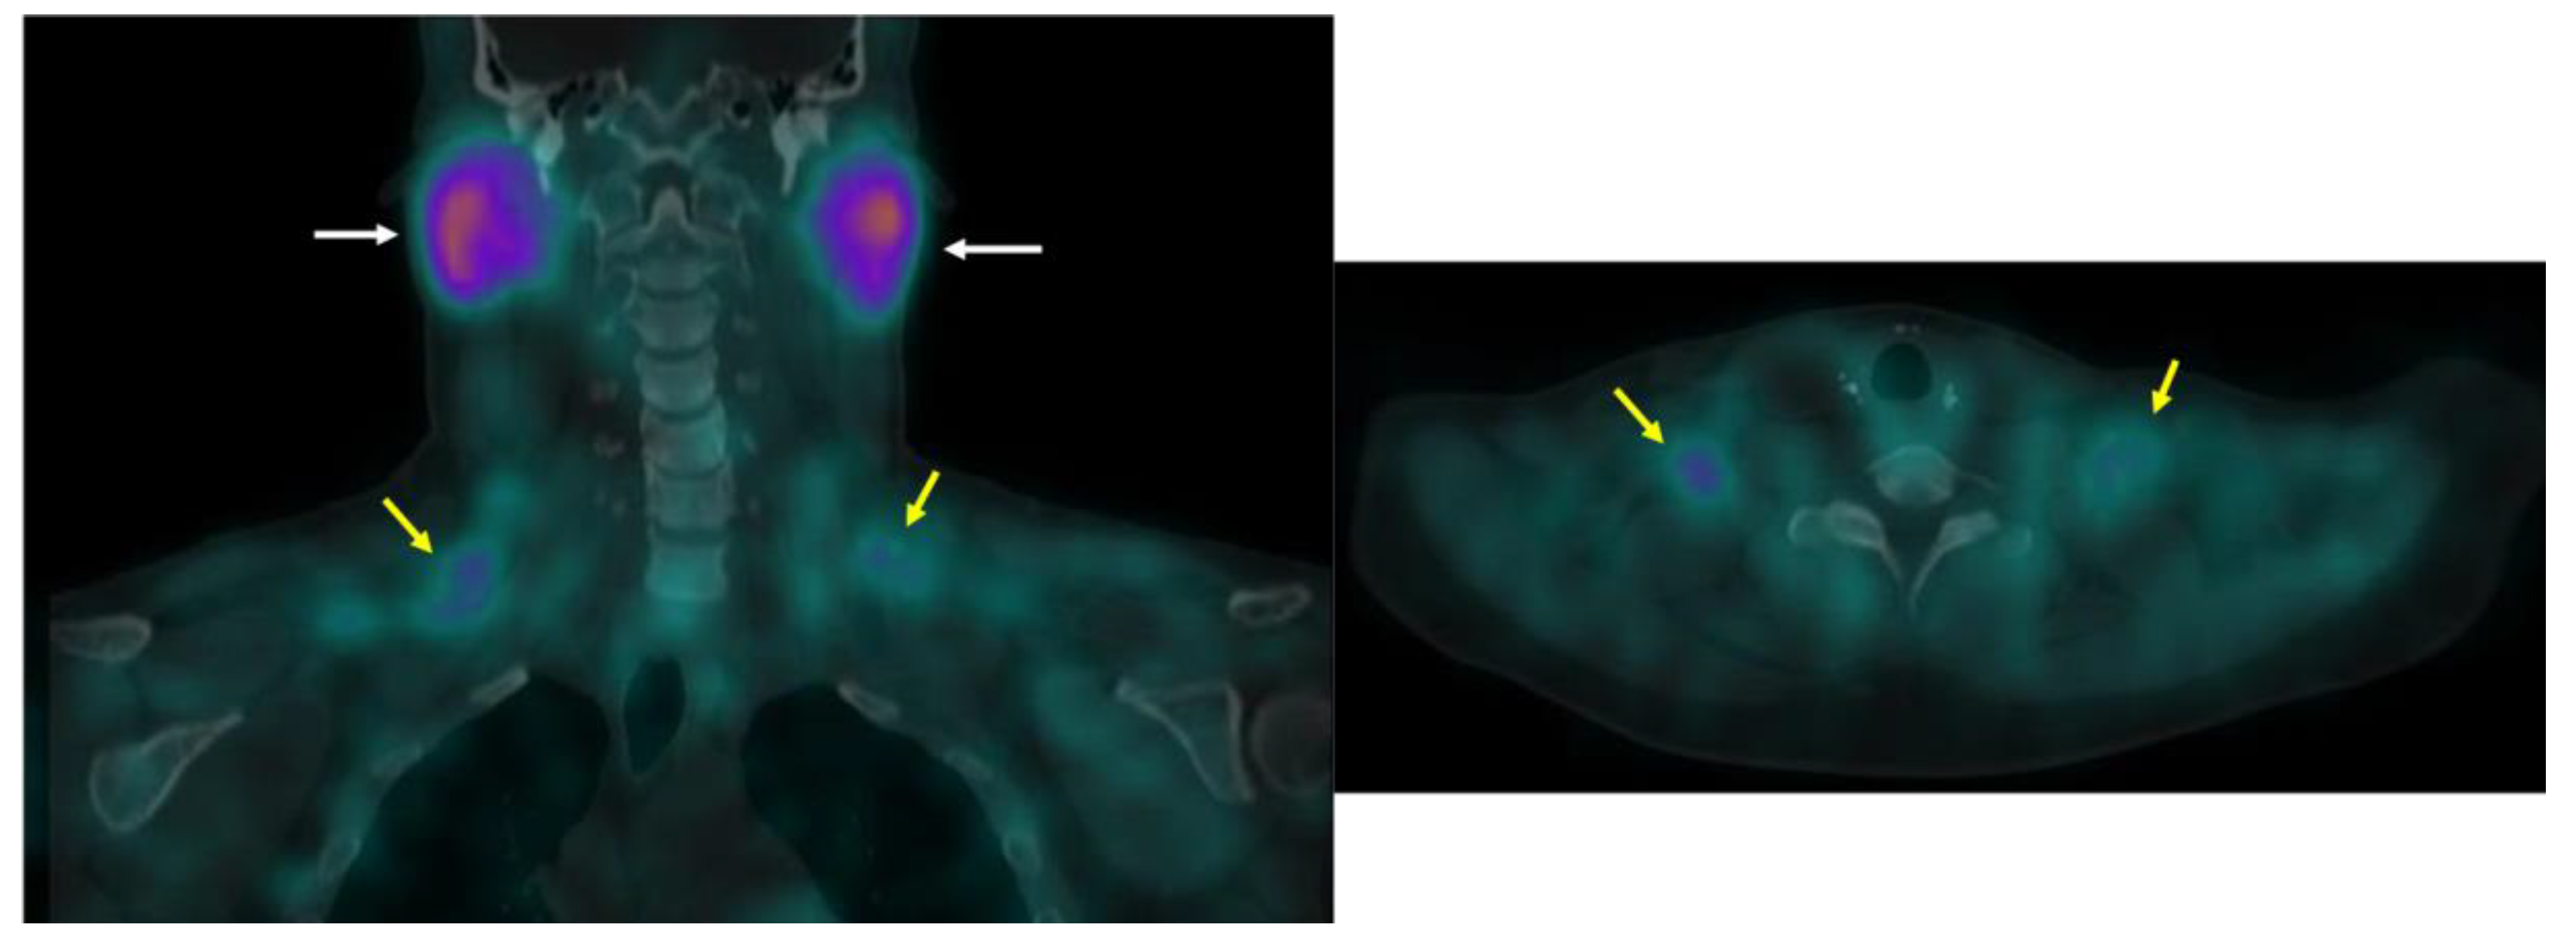

BAT is detected with other clinical and investigational radiotracers. 123I-metaiodobenzylguanidine (MIBG) SPECT/CT localizes sympathetic innervation by using a labeled norepinephrine analogue [75]. MIBG localizes BAT with similar sensitivity to FDG-PET/CT but is less temperature dependent [9,75,76]. The 11C PET tracer and norepinephrine analog 11C-meta-hydroxyephedrin has demonstrated sensitivity to BAT at thermoneutral conditions and its activity correlates with FDG uptake with acute cold in humans [77]. The commonly used SPECT/CT tracer 99mTc-methoxyisobutylisonitrile (MIBI), which localizes to tissues with high mitochondrial density, detects BAT in a non-temperature dependent manner as shown in an example from our clinical practice (Figure 9) [76,78]. 15O-labeled water PET/CT has been used in this setting to measure blood flow, which provides data to estimate tissue-specific metabolic rate using arterial oxygenation and known oxygen extraction fractions [77]. Din and colleagues combined 15O-labeled water PET/CT with inhaled 15O administration to directly measure tissue metabolic rate in humans [79]. The short (2 min) half-life of 15O allows for repeat PET scanning with another tracer on the same day [77,79]. Investigational radiotracer currently include the mitochondrial outer membrane translocator protein, visualized with 18F-FEPPA PET/CT and 11C-PBR28 PET/CT, the cannabinoid type 1 receptor, visualized with 18F-FMPEP-d2 PET/CT [80,81,82,83], and PD-L1, visualized with radiolabeled antibodies [84,85].

Figure 9.

99mTc-MIBI uptake in iBAT on a clinical scan. Supraclavicular BAT uptake shown coronal and axial fused 99mTc-MIBI-SPECT/CT (yellow arrows). Salivary gland uptake (white arrows) is normal.